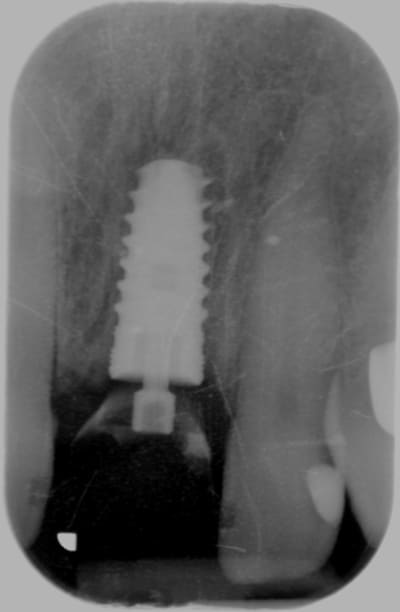

Allez, pour apporter mon caillou à la plage, un cas intéressant, d'implant en urgence.

consultation suite à une chute et fracture de 21 couronnée, un 29 Décembre, décision de poser l'implant le 31.12.

Extraction, mise en place d'un implant de 5*11.5 torque > 35N

Mise en place d'une dent provisoire transvisée.

Prothèse transvisée définitive à 3 mois.

Les 2 dernières photos à 1 an.

la photo ceram en place est à 6 mois. Noter l'amélioration des papilles entre 6 mois et 1 an...

non pas comblé pourtant hiatus assez important environ 1.5mm.

Longueur 11.5, mais j'aurais du mettre un plus long, pour la MCI j'aurais pris moins de risque...